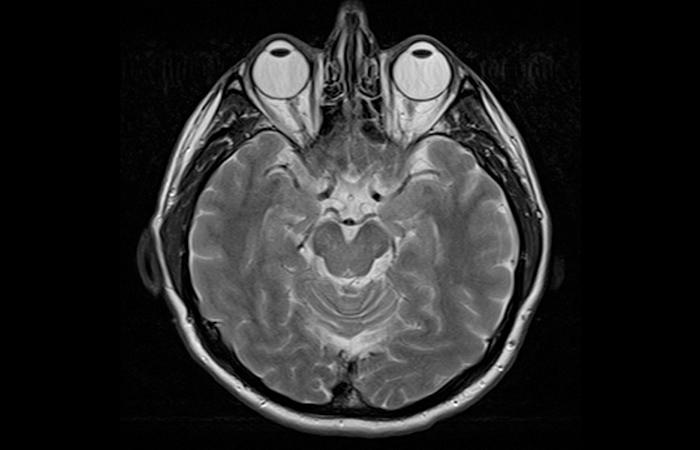

2. This Is How Your Brain Looks In An MRI

Source: Wikipedia Commons

We know you might have the impression that your brain resembles a walnut in terms of its shape and texture. But we are here to tell you that that’s not the complete truth.

While that image is used as a ready reference in textbooks and popular depictions, the image given above is what your doctor or medical students actually look at, when they study the most enigmatic of all human organs.